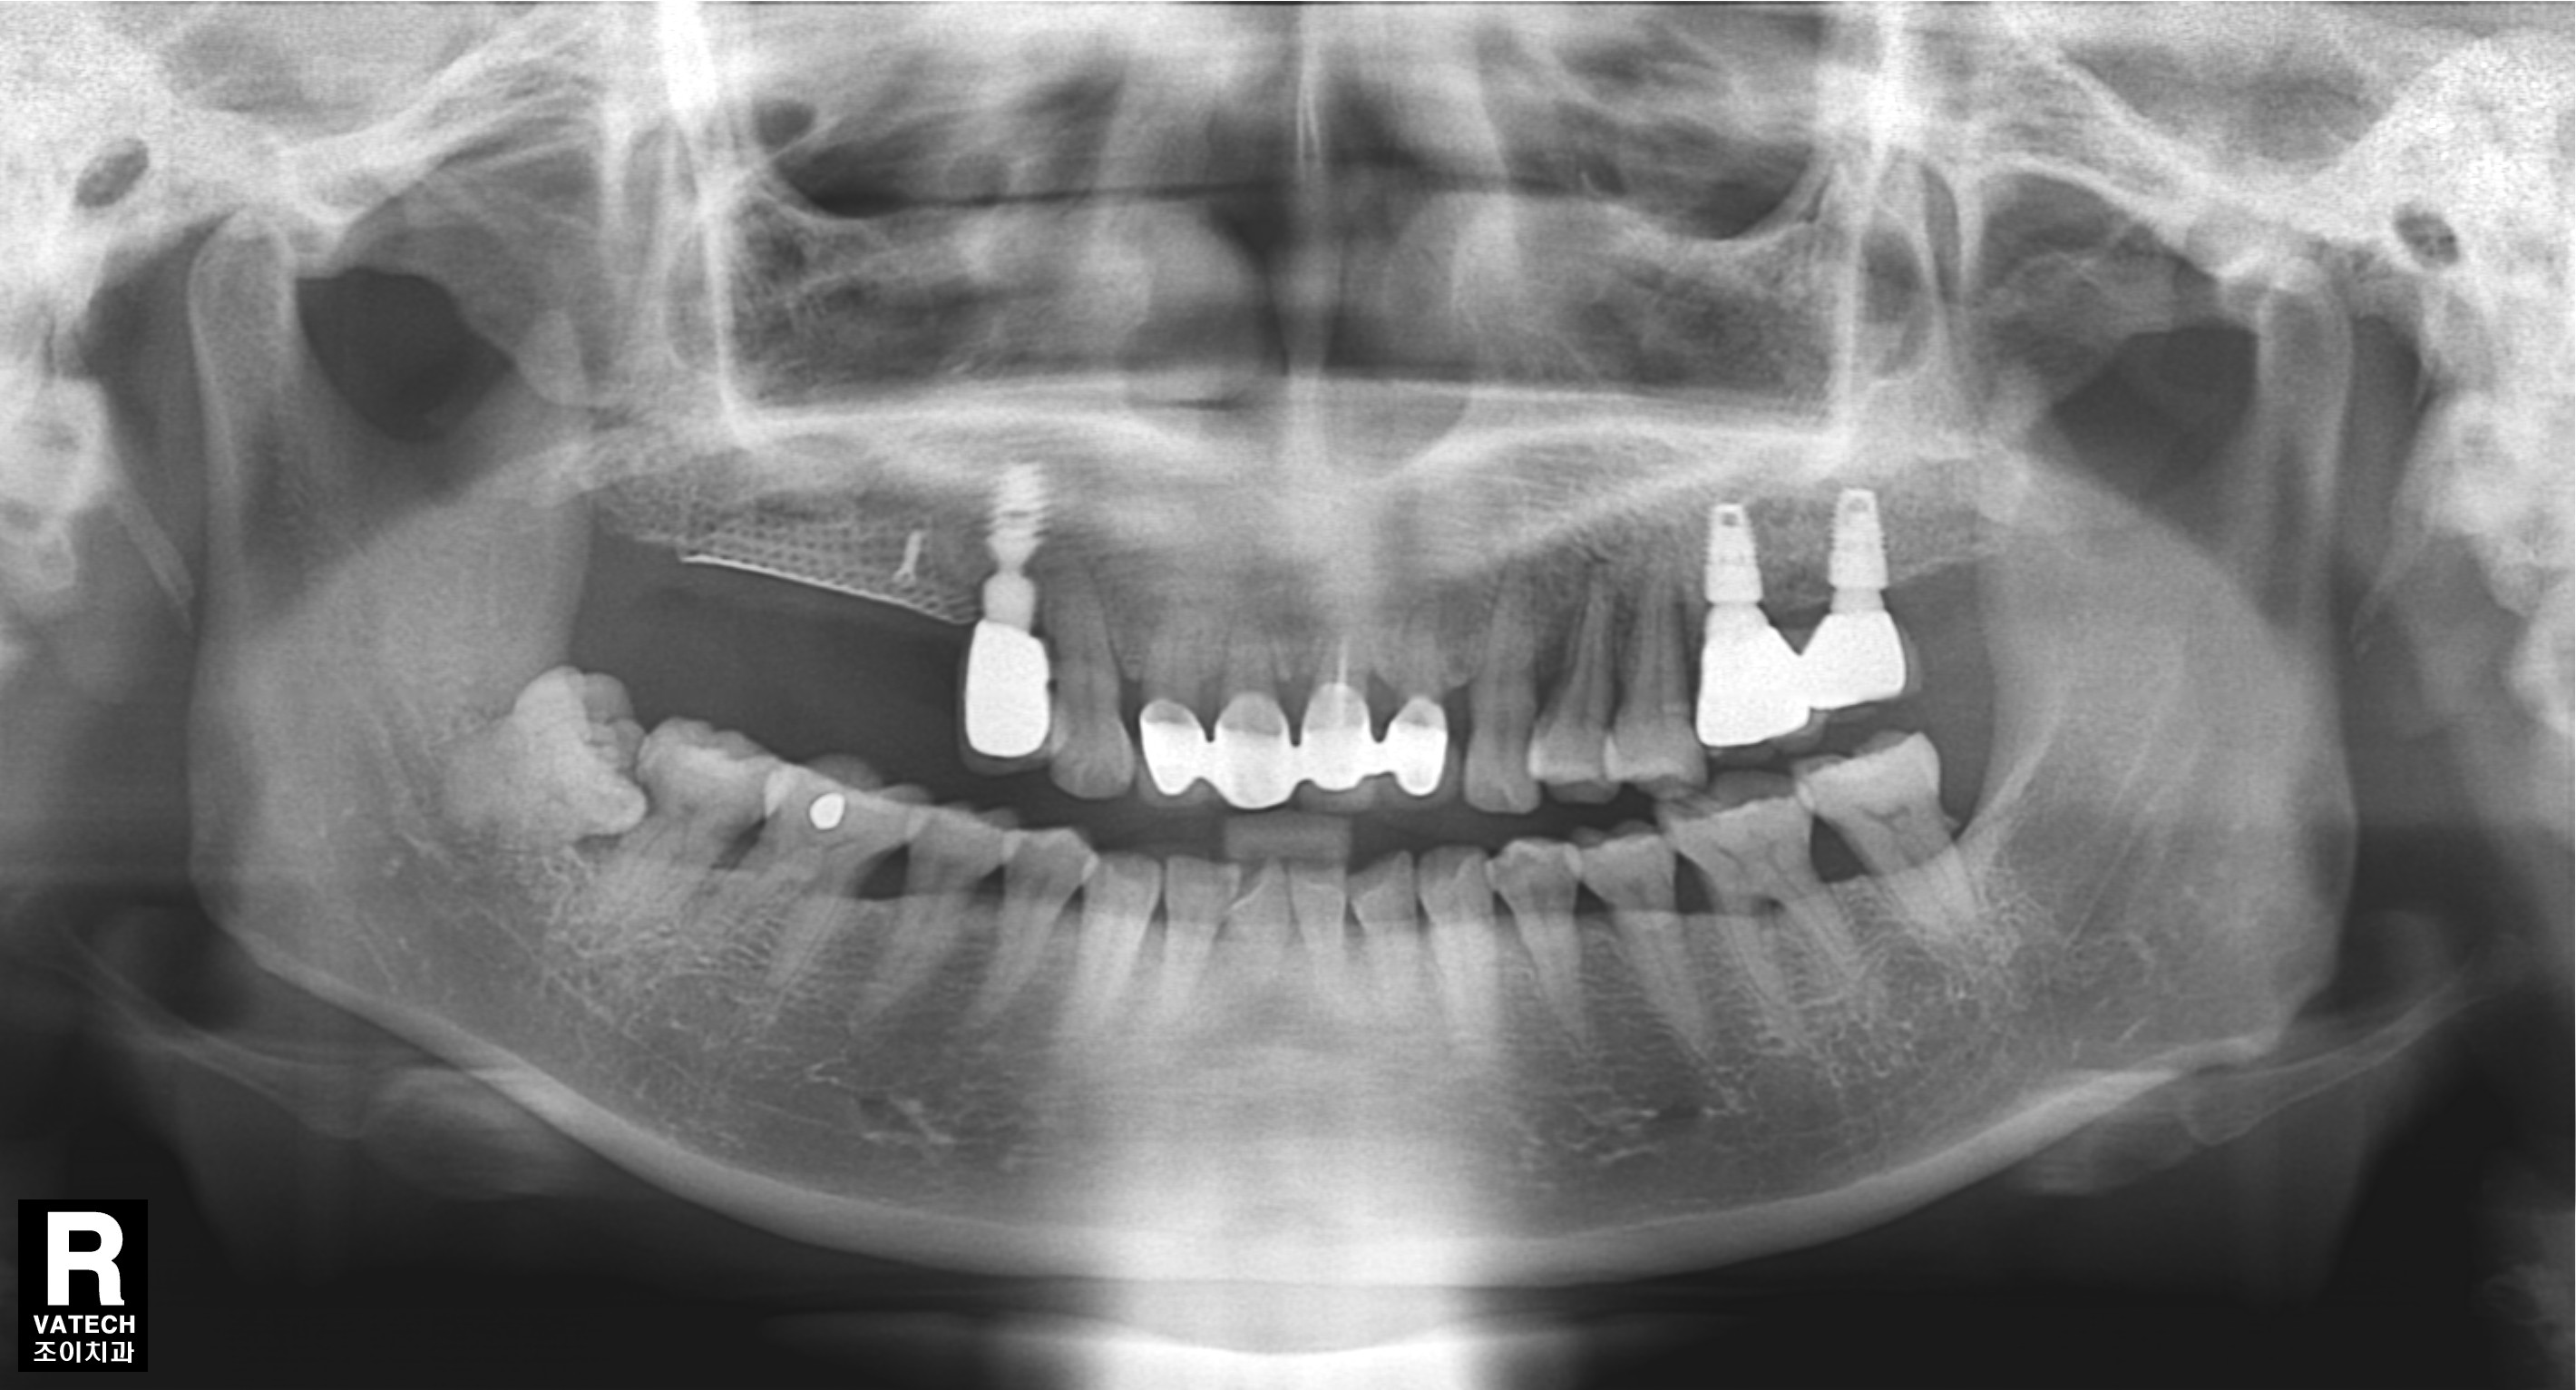

#15.16 부위로 타병원에서 수차례 실패했던 임플란트의 치료사례입니다.

임플란트 제거, 염증제거,티탄메쉬 골이식(bone graft), 서두르지 않고 충분한 경과관찰.

기본에 충실하게 step by step으로 다시 치료하는 것이 관건입니다.